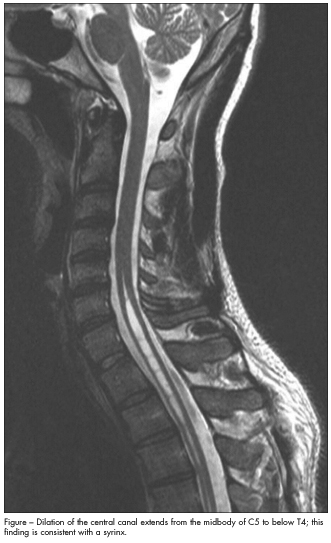

Axial and sagittal T2-weighted images show a dilation of the central canal that extends from the midbody of C5 to below T4—a finding consistent with a syrinx (Figure). The cerebellar tonsils are in the normal position (no Chiari malformation or tonsillar ectopia). No enhancement with intravenous contrast or intramedullary spinal cord mass is identified. The images point to an idiopathic syrinx—a syringomyelia.